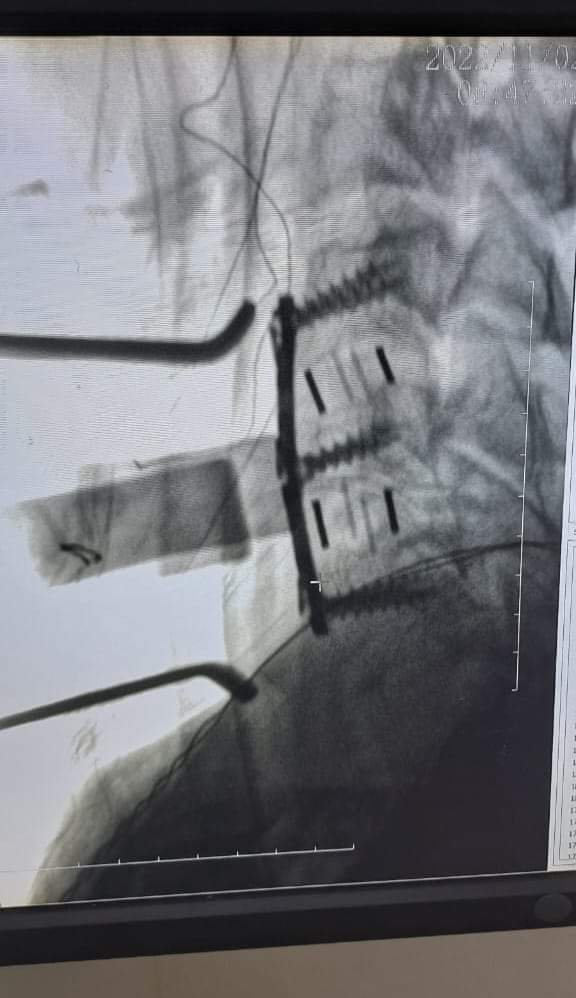

أجرى فريق الجراحة العصبية في البقاع، في مستشفى دار الأمل الجامعي، وبإشراف الدكتور حسان إبراهيم أمهز والدكتور رفيق حيدر، عملية نوعية لمريض يعاني من شلل في أطرافه الأربعة نتيجة خلع في الفقرات الرقبية، إثر تعرضه لحادث سير.

أجريت العملية باستخدام تقنيةNIM (NEURO MONITORING SYSTEM)،وهو من أحدث الأجهزة في المنطقة.

وقد تكللت العملية، بالنجاح الباهر بعودة الحركة للمريض وقدرته على المشي وتحريك كامل أطرافه.